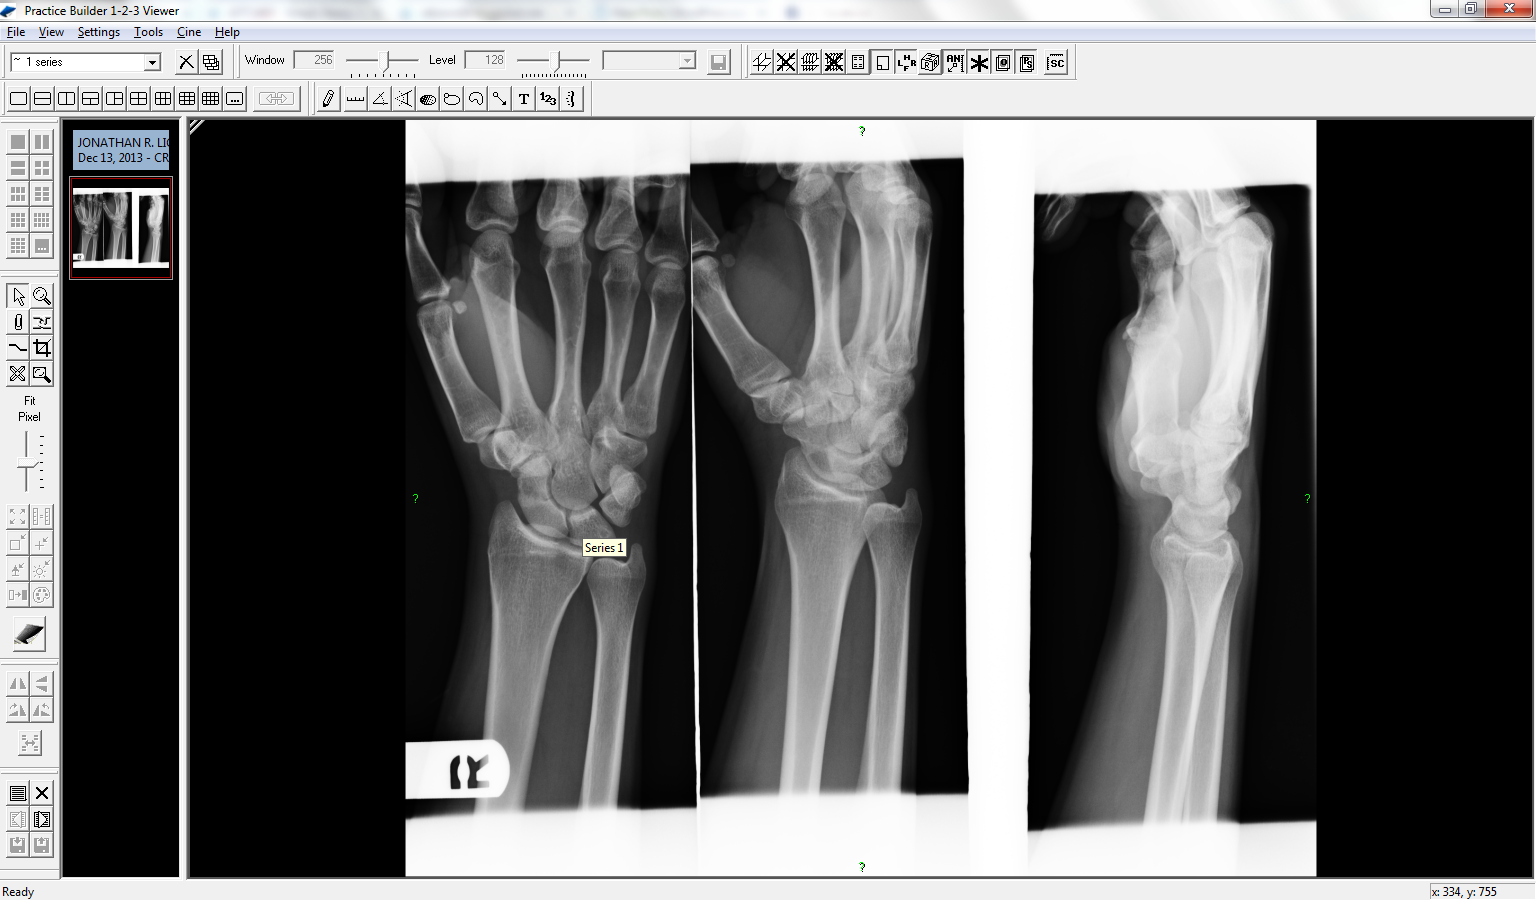

Fast forward to this past fall. In November I have two separate incidents, “sprain” both my hands. I finally go to the doctor. He agrees I probably have a sprain, but will do an x-ray just to add peace of mind. But the x-ray shows a fractured 4th metacarpal in the left had. So off to the bone doctor.

The bone doctor puts the left hand in a cast, and sends the right for an MRI. The x-ray has a shadow he cannot see as a fracture or not. Takes three weeks to get the MRI and back to the doctor around Christmas. I get back, get the cast off the left, but put a cast on the right. Seems it has a fractured scaphoid in the wrist. That cast stays on a month until Monday, where I now have a splint for another two weeks.